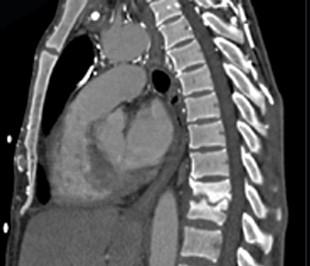

问题 男,36岁,腰背部疼痛,局部软组织肿胀,夜间加重,背部有过外伤史,有过结合图像,最可能的诊断是 ( )

选项 A、强直性脊柱炎 B、结核性骨髓炎 C、硬化型骨肉瘤 D、慢性骨髓炎 E、骨样骨瘤

答案 D